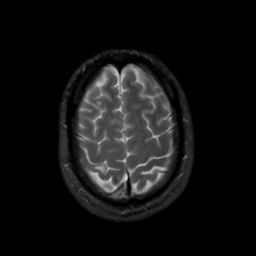

MR Study #4, March 3, 1991 -- Slice #42